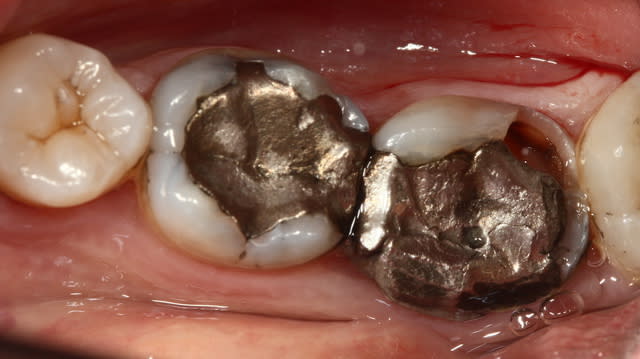

Oune plous pitite ...)))

La 16 est magnifique , le compo de la 4 également (le pan d'émail sert de point de contact , youpi)...

Patient habituel si on peut dire , pris en paro par ma femme , reparti chez un ami...à lui pour les prothèses , reviendu chez moi .

J'ai des bourrages , effectivement c'est ballot et à part refaire les cérams , je ne vois pas .

Pis chuis nul en composite , on va faire un onlay , c'est la seule soluce . Oui je vais en profiter parce que d'ici 2 ans je serai à la retraite , et la moutouelle...là on me rembourse tout . Je vais quand vous faire un devis à tout hasard...)))